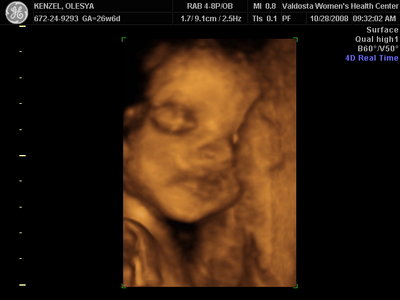

Еще одна Джианнка:

| Вложения: |

KENZEL,OLESYA_5.JPG [ 60.02 КБ | Просмотров: 1495 ]

Катюш, какой прикольный бутузик ! Олесь, после фотки средней - точно прям похожи!